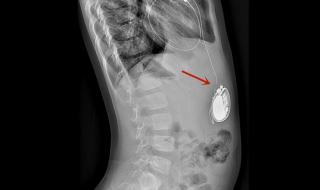

全磁浮心脏即离心泵人工心脏,被称为第三代人工心脏,是目前最先进,对人体影响最小也是最耐用的人工心脏,美国FDA前两年刚上市了第一款,我国高端医疗器械几乎无国产产品。

一、全磁浮人工心脏介绍全磁浮心脏即离心泵人工心脏,被称为第三代人工心脏,是目前最先进,对人体影响最小也是最耐用的人工心脏,美国FDA前两年刚上市了第一款,我国高端医疗器械几乎无国产产品。二、人工心脏电池容量为什么那么小1、人工心脏作为一种医